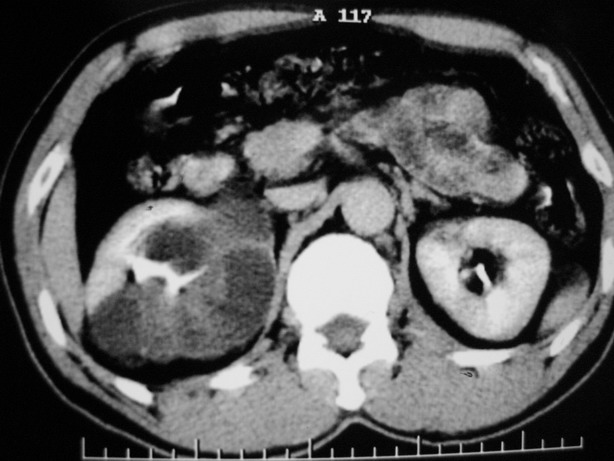

标题: CT10772:男性,48,右肾盂旁多囊性占位!

男性,48,体检发现,平时无症状。

平扫:

肾盂旁多囊性占位,有实性成分,增强有轻度强化,收集期病变内无造影剂显影。诊断肾盂旁囊肿,有实性成分无法解释,查书后诊断为:多房性囊性肾瘤!!不知大家同意否?????????对本病知道不多,望大家不吝赐教!!